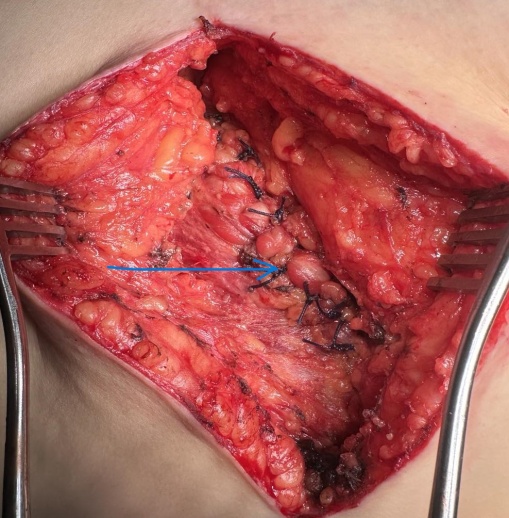

Λεπτό έντερο ελεύθερο μετά από μεθοδική αδρανοποίηση συμφύσεων (Ευγενική παραχώρηση Dr. V. Penopoulos)